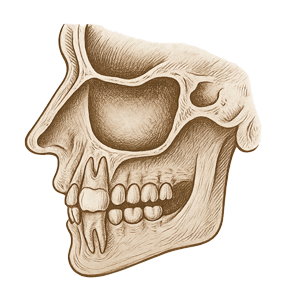

Diş Kaynaklı Sinüs Hastalıkları

Diş kaynaklı sinüs hastalıkları, özellikle üst çenede bulunan azı ve küçük azı dişlerinin köklerinin, maksiller sinüs boşluklarına olan yakınlığı nedeniyle oluşan problemleri kapsar. Enfekte ya da çürümüş dişlerin kök uçları, sinüs boşluğuna ulaşarak burada enfeksiyon gelişmesine neden olabilir. Bu durum genellikle “odontojenik sinüzit” olarak adlandırılır ve klasik sinüzitten farklı olarak kaynağı diştir.

Bu tür rahatsızlıklar, uzun süren yüz ağrısı, burun tıkanıklığı, geniz akıntısı ve tek taraflı baş ağrısı gibi belirtilerle kendini gösterebilir. Diş kaynaklı olduğu için çoğu zaman sadece burun tedavisi yeterli olmaz; sorunun kökenine yani dişe yönelik müdahale gereklidir. Kavi Diş Kliniği’nde bu gibi durumlar, panoramik röntgen ve gerektiğinde tomografi gibi ileri görüntüleme yöntemleriyle ayrıntılı şekilde değerlendirilir.

Tedavi, enfekte dişin çekimi, kanal tedavisi veya kök ucu rezeksiyonu gibi müdahaleleri içerebilir. Gerekli durumlarda kulak burun boğaz uzmanı ile iş birliği içinde multidisipliner bir tedavi süreci yürütülür. Sinüs sağlığını doğrudan etkileyen bu problemler, zamanında ve doğru şekilde tedavi edilmediğinde hem dental hem de sistemik komplikasyonlara yol açabilir. Bu nedenle ihmal edilmeden değerlendirilmesi gerekir.